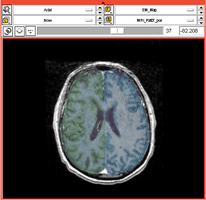

Comprehensive Longitudinal Investigation of Multiple Sclerosis at Brigham and Women’s Hospital (CLIMB) Study

- Collaborator: Svetlana Egorova MD/PhD (Brigham and Women's Hospital(BWH)), Alexander Zaitsev PhD (BWH)

- Short description: Provide Basic EM Segmentation for estimation of brain parenchymal fraction (BPF) . The processing is being performed for the cases with failing PD TDS+ segmentation. The T1-type scans are segmented and registered to PD/T2 images. The requests are being submitted over the Web GUI.

- Image specification: 1.5 Tesla ,Scanner: Varies among participants.

- Used Task: MRI Human Brain Hemisphere